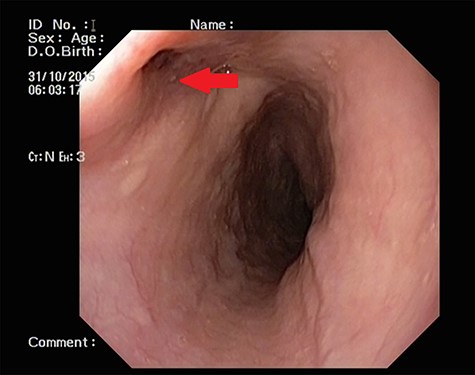

Patient 1: a 52-year-old woman, non-diabetic, non-hypertensive, was referred to the emergency with a history of large-volume, frank hematemesis (four episodes in 3 days). Positive history included recurrent cough for the past 1 year and low-grade fever for 3 months. No history of dysphagia, jaundice, abdominal distension, pain abdomen or altered sensorium. No history of chronic medications (oral anticoagulants or anti-platelets), analgesic intake or any substance abuse. She had received four units of packed red cells at an outside facility prior to admission. She was conscious, oriented, hemodynamically labile (heart rate: 110/min; BP: 86/60 mm Hg) with mild fever (99°F). General survey revealed obvious pallor. All other system examinations were within acceptable limits. Her hemoglobin (Hb) was 7.3 gram%, total leukocyte count (TLC) was 6400 cells/mm3, total bilirubin was 1.31 mg/dl and total protein was 4.75 gram%. An urgent UGI endoscopy revealed an opening in the posterior wall of the lower third of the esophagus, with a diverticulum. Inflammatory changes were noted in the diverticulum (Fig. 1). Contrast-enhanced computed tomogram (CECT) revealed erosion of the pouch into the thoracic aorta (Fig. 2), and a diagnosis of AEF with acute UGI hemorrhage was made.

CECT showing the descending thoracic aortic aneurysm; the red arrow shows the communication of the aneurysm with the esophagus.

Patient 2: a 48-year-old hypertensive, non-diabetic gentleman, presented to the emergency with one episode of massive hematemesis. There was no history of dysphagia, jaundice, abdominal distension, pain abdomen or altered sensorium. Past history was significant for percutaneous coronary intervention with two drug-eluting stents performed 3 years ago, for which he was on aspirin. He had normal mentation, his BP was 90/60 mm Hg and his heart rate was 120/min. A general survey revealed pallor and rest of the systemic examination was normal. His Hb was 6.1 gram% and TLC was 6300 cells/mm3. Liver function tests, coagulation parameters, renal function and electrolytes were normal. Chest X-ray was unremarkable. He was initially resuscitated with intravenous fluid, packed red blood cells and a proton-pump inhibitor infusion. An urgent UGI endoscopy revealed a large depressed ulcer with a red spot located in the middle third of the esophagus. A diverticulum was seen in the lower end of the ulcer (Fig. 7). An endoscopic clip was applied to the margin for ease of identification. CECT thorax revealed a 6 cm saccular thoracic aortic aneurysm distal to the left subclavian artery, eroding into the esophagus (Fig. 8).